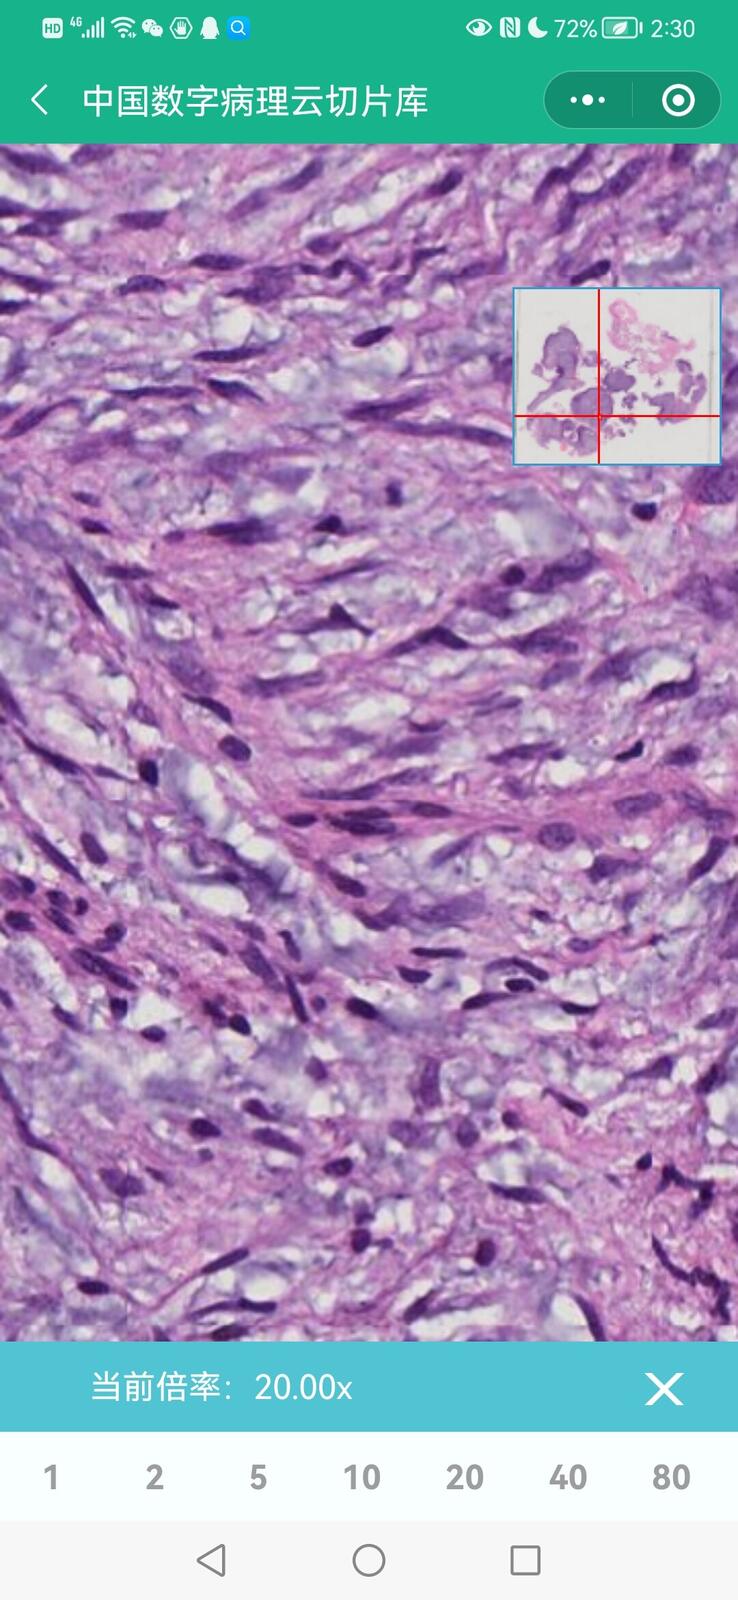

乳腺黏液性囊腺瘤伴导管内癌

乳腺多形性脂肪肉瘤

乳腺叶状囊肉瘤

乳腺分泌性癌(29岁)